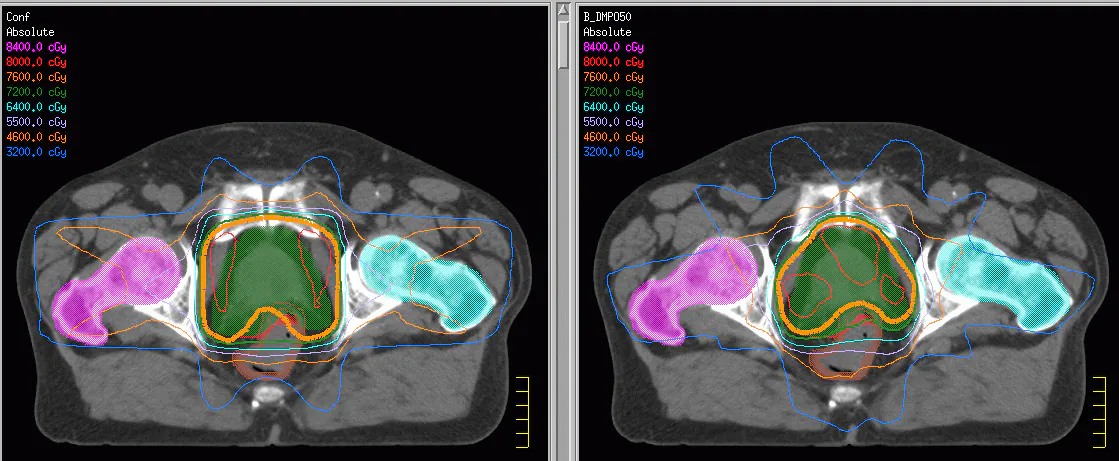

La radiothérapie, une dame de plus d’un siècle, tient une place majeure dans le traitement des cancers. L’enjeu ? Une guérison du plus grand nombre en limitant les effets secondaires. Les atouts ? Le couplage avec l’image, l’optimisation de l’irradiation, l’utilisation de nouvelles énergies (protonthérapie, hadronthérapie, etc.) et d’autres encore. Ces progrès se sont matérialisés par ce qui a été appelé dans les années 80-90 la radiothérapie conformationnelle 3D avec l’apparition de collimateurs multilames permettant de traiter des volumes cibles de formes complexes et de calculer les doses à délivrer en tenant compte des organes à protéger.

Le début du siècle a vu apparaitre la radiothérapie conformationnelle par modulation d’intensité (IMRT, où il est possible de moduler, au cours d’une séance de traitement, l’intensité des énergies délivrées afin de réduire la toxicité radio-induite. Le Cyberknife, constitué d’une source de rayonnements ionisants embarquée sur un bras robotisé à 6 degrés de liberté, offre un autre exemple de nouveautés où une grande flexibilité de ciblage et d’orientation des mini-faisceaux permet d’atteindre une précision géométrique de l’ordre du millimètre.

Les avancées en traitement et en analyse d’images proposées simultanément en recherche permettent aujourd’hui de prendre en compte les mouvements des organes et des cibles tumorales pour par exemple contrôler les faisceaux d’irradiation en fonction du cycle respiratoire. La radiothérapie guidée par l’image est ainsi devenue une technique de routine et les nouvelles plateformes couplent aujourd’hui scanner-X ou IRM aux instruments de radiothérapie. La radiothérapie adaptative d’application plus récente, consiste à adapter le plan de traitement à l’évolution des tumeurs tout au long des séances.